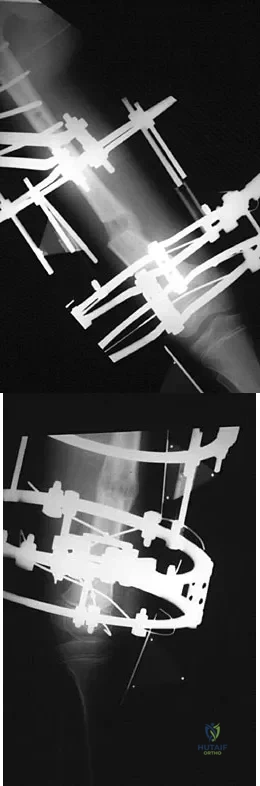

A teenager is undergoing a correction of deformity and lengthening of the femur. Distractions are proceeding as expected; however, during his 6-week follow-up examination, the patient reports that the distraction motors have become harder to turn over for the past 2 to 3 days. Figures 37a and 37b show current radiographs. What is the most likely complication being encountered?